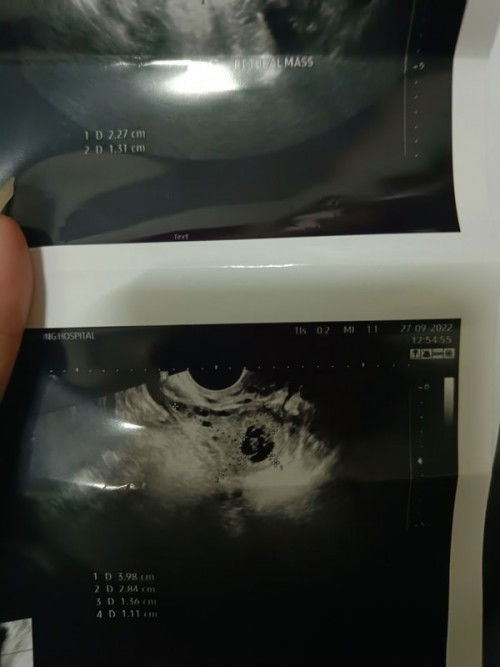

อยากจะถามแม่ๆว่าใครเคยเจอเหตุการณ์แบบนี้บ้างคะคือกลัวมาก กังวล วันศุกร์ตอนเช้าตื่นนอนลุกขึ้นไปฉี่มีอาการจุกท้องน้อยมากจุกไปถึงทวารพอบ่ายมาปวดท้องมากมีเลือดไหลออกมาไม่เยอะ พอไปหาหมอแต่ไม่ใช่หมอสูตินะคะ เขาก็อัลตร้าซาวด์ดูแต่หมอบอกไม่พบถุงตั้งครรภ์ แต่เราพึ่งท้องได้ประมาณ4สัปดาห์ เขาสงสัยว่าจะท้องนอกมดลูกค่ะ คือท้อง4สัปดาห์ อัลตร้าซาวด์เจอถุงตั้งครรภ์ไหมคะ ยังมีหวังจะปลอดภัยไหม วันนี้ก็ยังมีเลือดไหลอยู่ค่ะเป็นสีน้ำตาลแต่ไม่มาก รพ.นัดตรวจอีกทีกับหมอสูติอีก2วันค่ะ#ขอบคุณล่วงหน้านะคะ